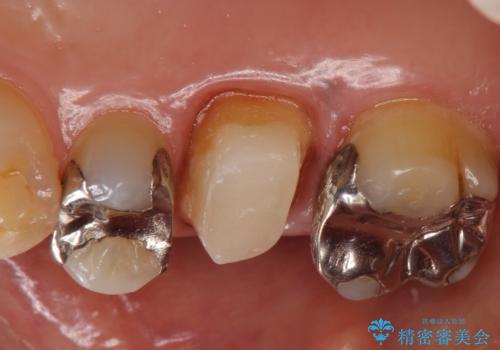

- 右上6番目の銀歯と歯茎の間に隙間ができているのが気になるので診て欲しいといらっしゃった方の症例です。

根管治療も希望されたため、再根管治療終了後、オールセラミッククラウンによる補綴を行いました。

- オールセラミッククラウン…¥100,000、仮歯…¥10,000、ファイバーコア…¥20,000費用は治療当時の料金となります